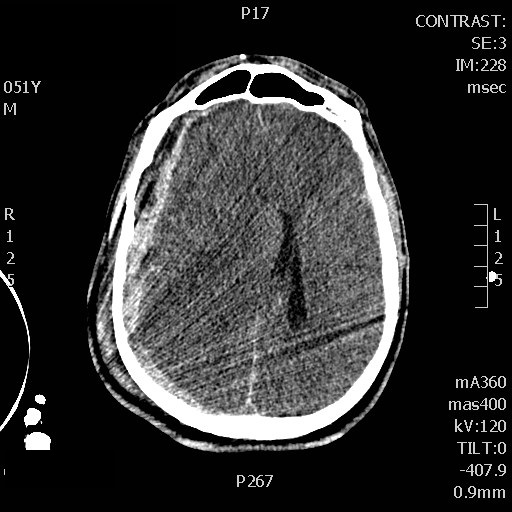

Also, I was able to record a baseline internal carotid doppler waveform in the first minutes of rescucitation showing a markedly reduced diastolic flow (wasn’t able to find a vessel by TCD). I subsequently noticed improvement of the waveform following administration of mannitol which prompted me to be more agressive on the hyperosmolar therapy (started an hypertonic saline drip) despite the absence of clinical improvement at that time. In the next few hours, the patient waveforms further improved and the patient started withdrawing to pain.

2) Assessment of the response to hyperosmolar therapy before clinical response is apparent, or in the paralysed patient.